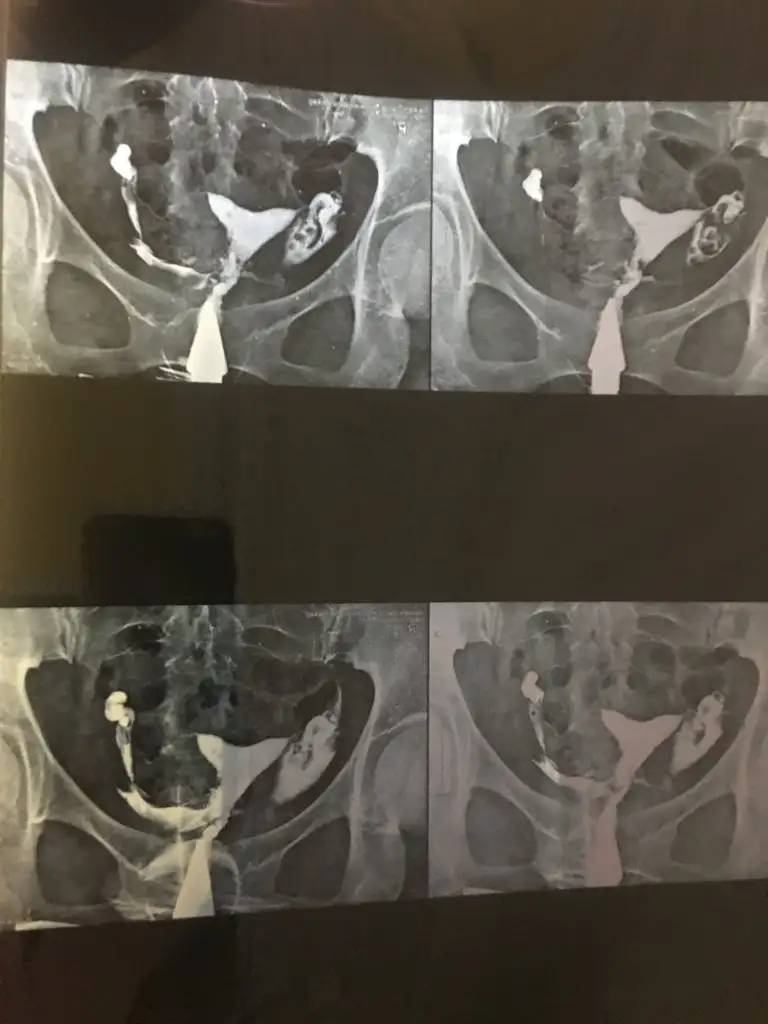

Mayısta ekteki rahim filmini çekilmiştim ve beni takip eden doktorum 2 tüpümün birinde sıvı olduğunu ve laparoskopi yapacağını aynı zamanda rahimdeki ufak tefek yapışıklık için de aynı zamanda da histeroskopi yapacağını söylemişti ve adet olmayı bekliyordum işlem için

(Geçen yaz tüp bebek ile 10 haftalık 3üz kürtajım olmuştu kalpleri durmuştu hepsinin ve hsg sonrası kalp durma nedenlerinin bu sıvıdan kaynaklı olacağını söyledi)

Bugün 2. Bir görüş almak adına Cevat bayrak hocaya da attım ekteki hsg rahim filmimi

Cevat hoca hidrosalpenks yok iki tüpte de sadece rahimde ufak yerlerde yapışıklıklar var histeroskopi önerebilirim diye yazmış

Şimdi ben çok kararsız kaldım zaten ameliyat korkumda var ne yapmalıyım sizce bir akıl verin lütfen bana